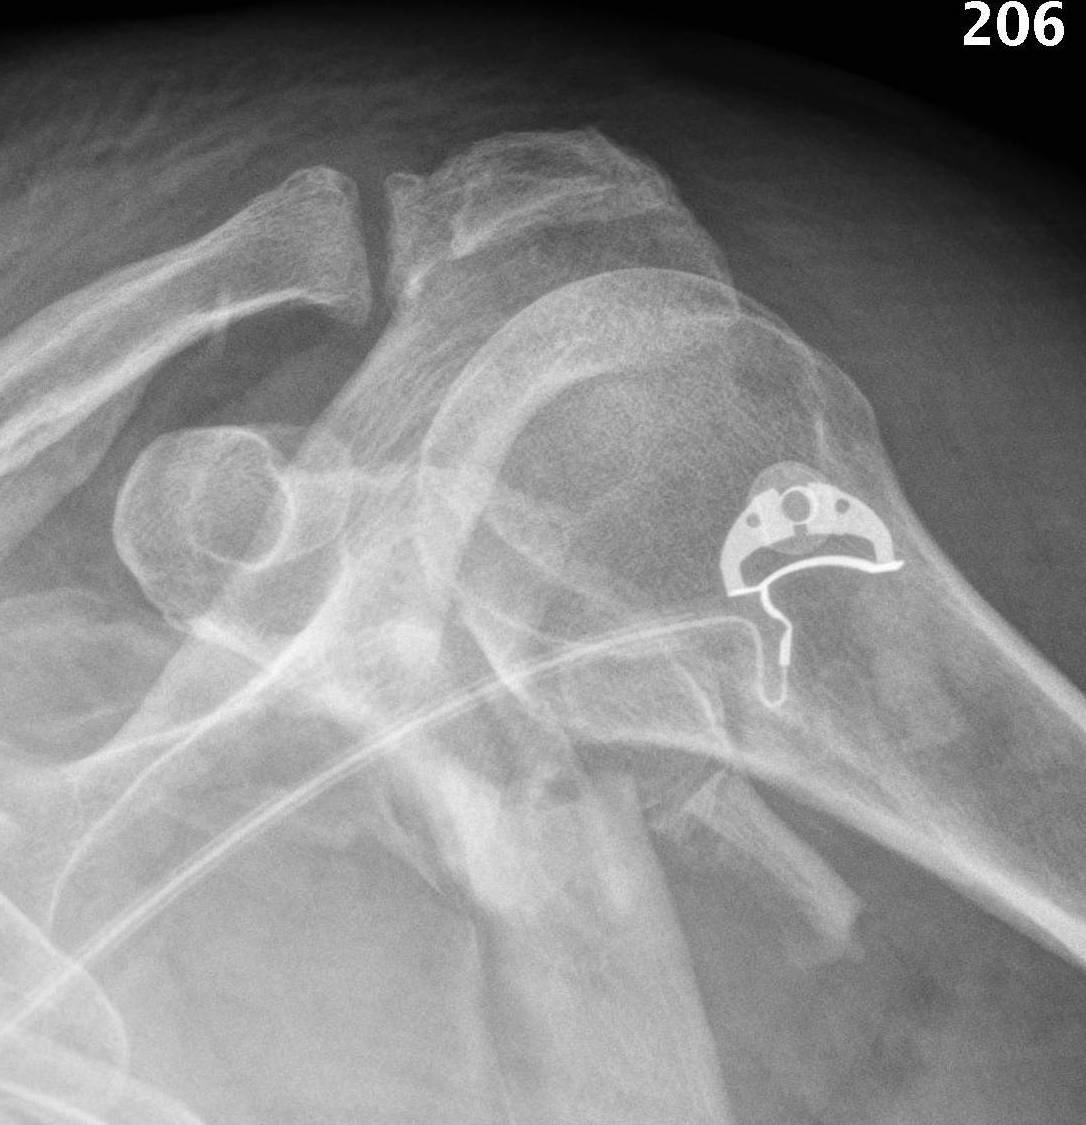

Type IA: Anterior glenoid rim fracture

Xray / CT